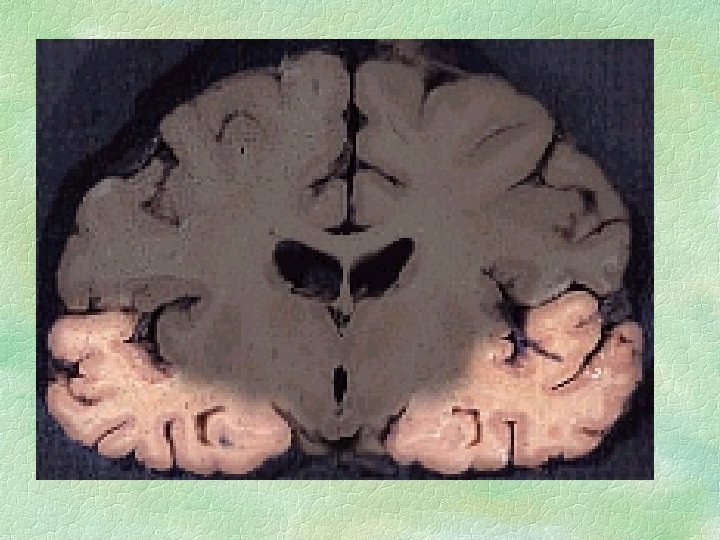

Diagrams from Raine’s research

Raine found some significant results § He suggested there was evidence for DIFFERENCES in the brains of the murderers § He found amongst other things LOWER ACTIVITY in some CORTICAL REGIONS of the brain

SUMMARY OF DIFFERENCES in the brains of the murderers § Reduced activity in prefrontal cortex, parietal region & corpus callosum § Left hemisphere less activity than right § Abnormal asymmetries in amygdala & thalamus